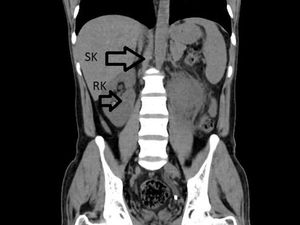

Pria 31 Tahun Niat Berobat gegara ISK Parah, Dokter Malah Temukan Ginjal Ketiga

Seorang pria 31 tahun pergi ke RS untuk mengobati infeksi saluran kemih yang parah. Namun, dokter malah menemukan ada ginjal ketiga di dalam tubuhnya.